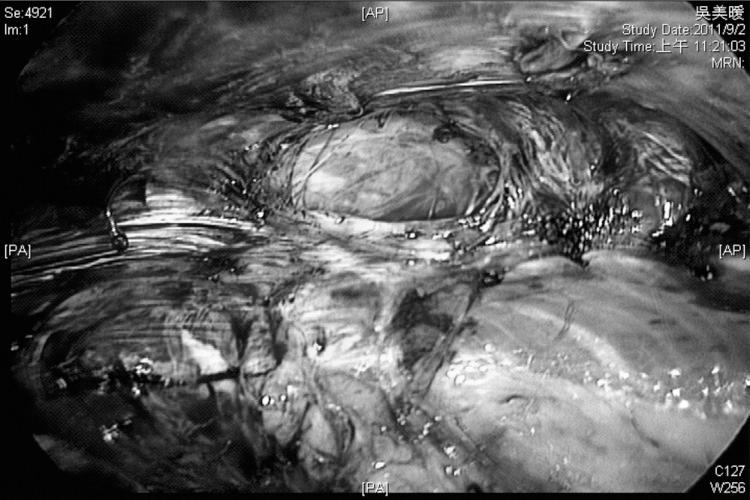

Three patients with incisional hernias after gynecologic surgery underwent laparoendoscopic single-site totally extraperitoneal procedures. We evaluated the patients' preoperative and postoperative condition, as well as the details of their original surgery. We performed the procedure through a 2-cm umbilical incision followed by mesh insertion and transabdominal suture placement in all patients.

Laparoendoscopic single-site totally extraperitoneal herniorrhaphy was completed in 80 to 120 minutes. No intraoperative complications were encountered, and surgical blood loss was minimal. The duration of hospital stay ranged from 2 to 4 days. One patient had a postoperative wound infection. The patients have shown no sign of recurrence at 9 months' follow-up.